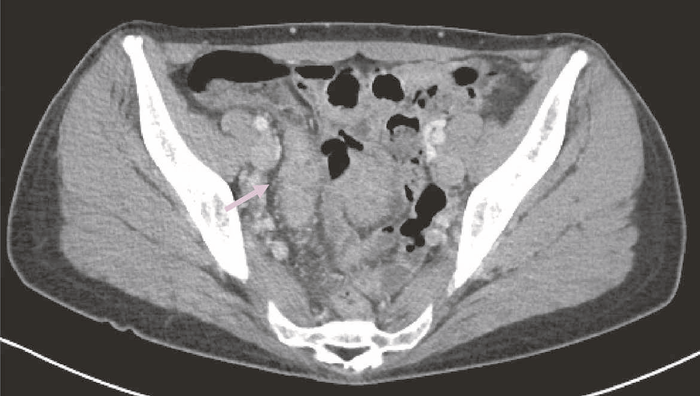

症例1 回腸癌(40歳代女性)

2年前にUCと診断されたが,1年前に,痔瘻の悪化と内視鏡検査で回腸末端に縦走潰瘍を認め,CDと診断された。adalimumabで治療が開始され,治療効果判定目的に施行した内視鏡検査で回腸に潰瘍を認め,生検でadenocarcinomaと診断された(内視鏡画像なし)。

図34 術前CT

術前CTでは回腸末端の壁肥厚を認め,周囲リンパ節の腫大は明らかではなかった。